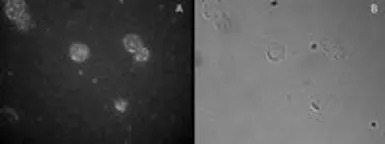

ICC/IF analysis of CD25-sorted (Treg) human blood cells using GTX89934 FOXP3 antibody, C-term.

A: Primary antibody and FITC conjigated secondary antibody, B: Phase contrast.